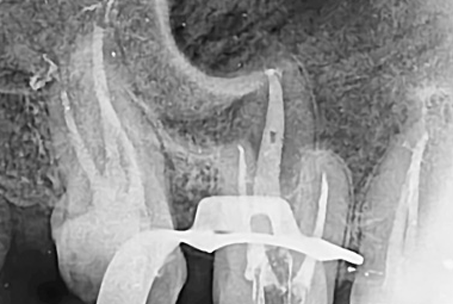

크라운과 기존의 신경관 충전물질을 제거 후

다시 신경치료를 진행하는 술식입니다.

일반적인 신경치료보다 어렵고 성공률이 떨어지기 때문에

전문적인 치료가 필요합니다.

특히 신경관이 막혀있거나 신경관에 POST가 박혀있는 경우

재신경 치료의 난이도는

매우 높아지며, 많은 환자분들이

재신경치료가 불가능하다며 발치를 권유 받습니다.

하지만 웃는얼굴치과에서는 특수 초음파 기구로 막힌

신경관을 찾거나

신경관에 박혀있는 POST를 제거한 후

재신경치료를 하여

환자분들의 치아를 살려드리고 있습니다.